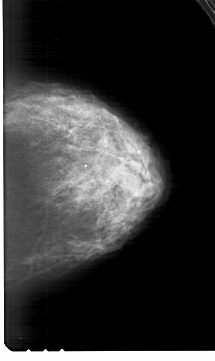

A_1983_1.LEFT_MLO

LEFT_MLO LINES 6421 PIXELS_PER_LINE 3886 BITS_PER_PIXEL 12 RESOLUTION 43.5 OVERLAY